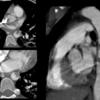

Min Aortic Injury

Date: 08/14/2012

Views: 2259